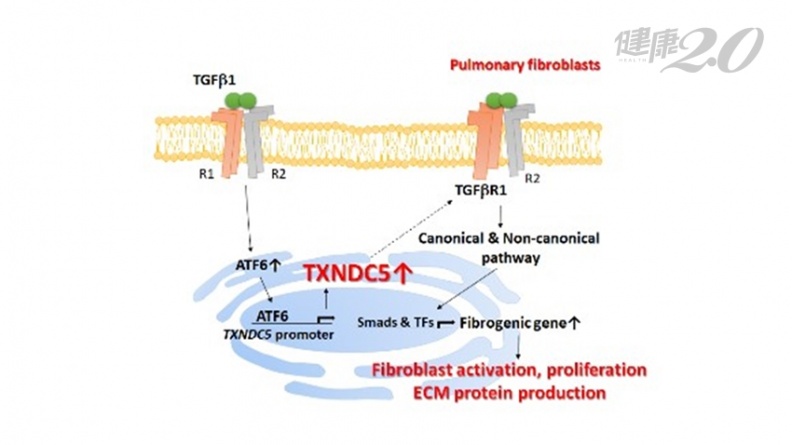

楊鎧鍵表示,研究發現,內質網蛋白「TXNDC5」是透過影響肺纖維母細胞中「TGFbeta receptor I」的穩定性及表現量來強化「TGFbeta」訊息傳遞路徑,造成肺纖維母細胞的大量活化增生及胞外基質堆積,引起肺纖維化。

▲內質網蛋白「TXNDC5」造成肺纖維化的致病機轉。